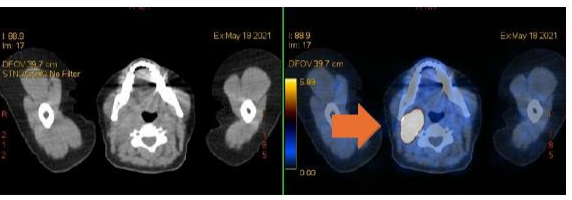

As a complementary study, a thoraco-abdominal-pelvic CT scan was performed, which showed multiple bilateral pulmonary nodular lesions, with a maximum diameter of 6 mm, suggestive of metastases. The Gallium-68-DOTA-TOC positron emission tomography (PET) scan revealed abnormal uptake with abnormal overexpression of somatostatin receptors in the right lateral cervical mass (image 3), in the pulmonary nodules, and in bilateral mediastinal-hilar lymph nodes.

Figure 3: Abnormal uptake with abnormal overexpression of somatostatin receptors in the right lateral cervical mass in the Gallium-68-DOTA-TOC PET (orange arrow).